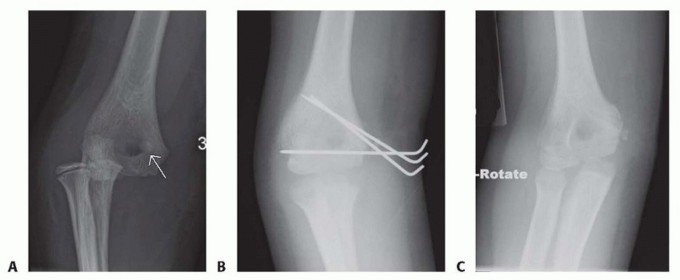

Intra-articular incarceration of the medial epicondyle is an absolute surgical emergency. This typically occurs following an elbow dislocation; as the joint reduces, the epicondyle and its attached soft tissues are sucked into the ulnohumeral articulation. Attempting closed extraction via joint manipulation is fraught with risk, including iatrogenic ulnar nerve injury and further cartilaginous damage, making open extraction and fixation the standard of care.

Pre-Operative Planning, Templating, and Patient Positioning

Meticulous preoperative planning is the foundation of a smoothly executed surgical procedure. The planning phase begins with a comprehensive radiographic evaluation. Standard anteroposterior (AP) and true lateral radiographs of the elbow are mandatory. However, because the medial epicondyle sits posteromedially on the distal humerus, standard AP views often obscure the true magnitude of displacement. Therefore, an internal oblique view is highly recommended to profile the medial column. Furthermore, a gravity valgus stress radiograph can be utilized to dynamically assess medial collateral ligament competence and occult fracture displacement.

In cases of significant comminution, suspected intra-articular incarceration that is ambiguous on plain films, or when evaluating a chronic nonunion, advanced imaging is warranted. A non-contrast Computed Tomography (CT) scan with 3D reconstructions provides invaluable information regarding the precise size, geometry, and rotational orientation of the fracture fragment, as well as the available bone stock in the distal humeral metaphysis for screw purchase. Magnetic Resonance Imaging (MRI) is less commonly required for acute fractures but is exceptionally useful for evaluating the integrity of the UCL and the flexor-pronator origin in subacute or chronic presentations.

5. Provisional Fixation

Once anatomical reduction is achieved, it is provisionally stabilized using 1.6 mm or 2.0 mm Kirschner wires (K-wires) or the guide pins from a cannulated screw system. The trajectory of these pins is absolutely critical. The starting point is on the anterior-inferior aspect of the medial epicondyle. The pins are directed superiorly, laterally, and anteriorly into the distal humeral metaphysis.

Directing the pins anteriorly is paramount to avoid penetrating the olecranon fossa. A second pin is highly recommended to provide rotational stability during the subsequent drilling and tapping phases. Following pin placement, the reduction and pin trajectory are rigorously evaluated using orthogonal AP and lateral fluoroscopy. The elbow is taken through a gentle range of motion under live fluoroscopy to confirm that the hardware does not impinge on the joint and that the reduction remains stable under dynamic stress.

6. Definitive Fixation

For definitive fixation, a 4.0 mm or 4.5 mm partially threaded cannulated screw is the gold standard. The appropriate screw length is determined using a depth gauge over the primary guide pin. The lateral cortex of the humerus should ideally be engaged to maximize pull-out strength, particularly in older patients or those with osteopenic bone.

The outer cortex of the epicondyle is overdrilled to create a gliding hole, facilitating interfragmentary compression. The screw is then advanced over the guide wire. If the epicondylar fragment is comminuted or if the patient is very young with a soft, cartilaginous apophysis, a spiked ligament washer or a standard low-profile washer should be utilized to distribute the compressive forces and prevent the screw head from burying into the fragment.

Once the primary screw is seated and excellent compression is achieved, the secondary anti-rotation K-wire is typically removed, unless the fragment is highly unstable, in which case it may be exchanged for a smaller secondary screw. Final fluoroscopic images are obtained to verify anatomical reduction, appropriate hardware length, and clearance of the olecranon fossa. The ulnar nerve is inspected one final time to ensure it is free from tension or hardware impingement before the wound is closed in layers.